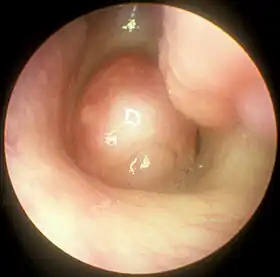

![]() Large nasal polyp (round mass, center), which is commonly treated and removed by FESS | |